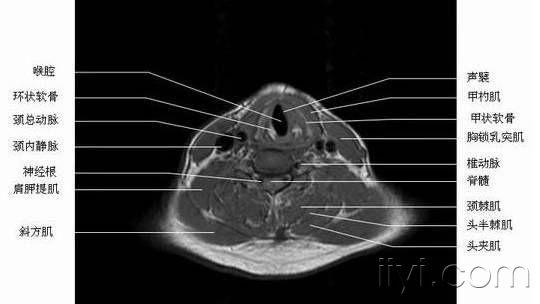

咽喉的正常ct解剖--原创,觉得有用请顶一下!

喉的选择性ct断层解剖!

喉的断层ct解剖

【影像解剖】喉部ct解剖---简单!